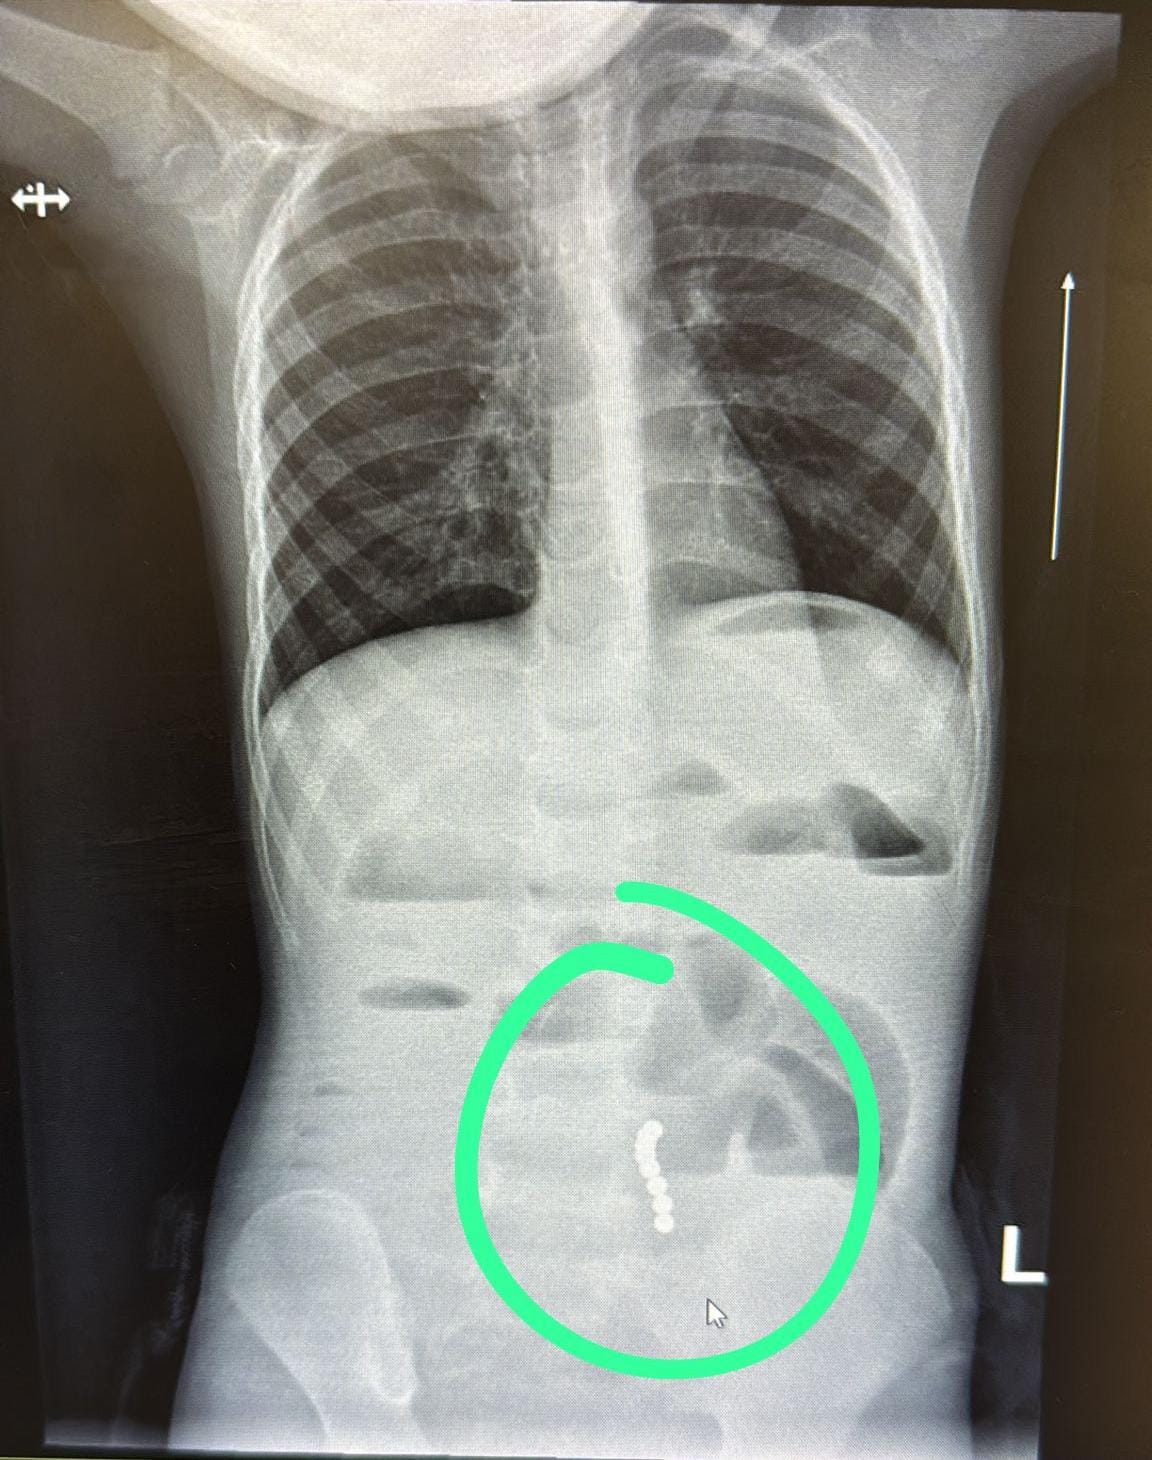

ד”ר ליאת יניב, רופאה בכירה במחלקת ילדים במרכז הרפואי בני ציון, זיהתה כי מדובר בהקאות ללא שלשולים ובעלות צבע חריג, ממצא שעורר חשד לבעיה משמעותית במערכת העיכול. בצילום הדמיה שבוצע בדחיפות, הודגמו מגנטים במעי הדק עם עדות לחסימת מעי.

בהתייעצות עם ד"ר ראוף נאסר, מומחה גסטרו ילדים, הפעוט הופנה להמשך טיפול כירורגי ונותח באופן דחוף ע"י ד”ר דניאל דובין, סגן מנהלת מחלקת כירורגיית ילדים במרכז הרפואי בני ציון ו ד"ר יאיר בן שמואל, רופא בכיר בכירורגיית ילדים, כאשר ד"ר אבו ראס עומר היה הרופא המרדים הבכיר. בניתוח הוצאו שמונה כדורי מגנט מהמעי הדק.